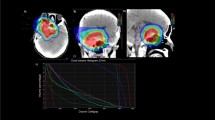

Specific data generated in the active research funded projects includes results on the potential of PET-CT 11-methionine/DOPA studies for improved contouring at the time of simulation and radiotherapy treatment planning to implement biology guided dosimetric prescriptions for pencil beam proton therapy technology [29]. Results in 17/17 patients diagnosed with primary or recurrent CNS tumors, showed areas of metabolism within the neoplasia range and showed a differential distribution of the tracer to guide boost delineation [30].

The research project more actively reported in our group is VASA (VAsos & SAngre; vessels & blood) [31, 32]. Craniospinal irradiation in medulloblastoma patients induces significantly less severe lymphopenia in children treated with protons compared to photons [33]. Furthermore, PBT increases levels of biomarkers related to vascular and endothelial radiation effects [34]. The search of vascular and immune biomarkers levels belongs to a work-in-progress long-term project assessing the development of a dose-volume-histogram applicable to standard clinical practice considering vessels and circulating blood as a very relevant organs-at-risk, in particular when alternative PBT is available. The potential of EDIC (the effective dose to circulating immune cells) as an independent predictive factor for hematologic toxicity is being investigated. Existing conventional imaging resources for dosimetric planning allow segmentation of vascular structures for accurate estimates of vascular DVH and blood dynamics. In our program, the most updated information generated in the period from November 2020 to April 2022, includes 54 patients treated with a radiotherapy component were prospectively analyzed in terms of dosimetric prescriptions. 4D MRI-flow sequences were exported for segmentation of the arterial and venous vascular tree up to a vessel diameter of 2 mm. Vascular and solid organ dose-volume histograms (DVH) were generated to calculate the EDIC as a ratio of blood flow based on the mean dose. In addition, the integral body and vessels dose were calculated by defining them as ID [Gy⋅L] = D [Gy]⋅V [L], where D [Gy] is the mean dose given to the volume V [L]. The mean PTV volume was 315 cc (± 157 cc). The mean vascular segmentation volume was 70 cc. The mean EDIC was 1 Gy. The mean body and vessel ID were 55 Gy*L and 1 Gy*L respectively. Frequency analysis showed that patients with higher EDIC correlated with vessel ID greater than 1 Gy*L. Quantifying irradiation exposure of circulating blood is feasible and requires the incorporation of high quality imaging of vascular structures for specific estimates of DVH and the implication in blood dynamics [32].

Pastor SM, Calvo FA, Garcia-Consuegra A, Andreu JS, Lostao JA, Gallego J, et al. 11C-Methionine-PET scan for target delineation in patients treated with IMPT for CNS tumors. Radiother Oncol. 2021;161(Supplement 1):2.

Palma J, Aristu J, Martín S, Serrano J, Meiriño R, Cambeiro M, et al. 11c-methionine & 18f–3,4-dihydroxyphenylalanine-pet-ct for target boost delineation in brain tumors. Clin Transl Oncol. 2022;24(Extraord. 1):163.